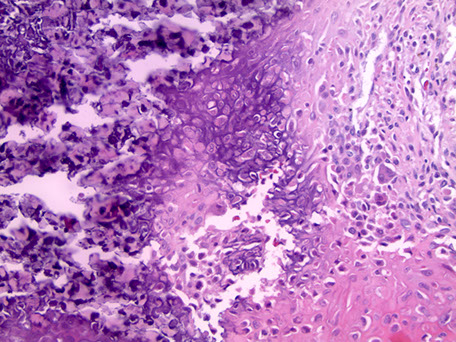

Aneurysmal bone cyst (ABC)

- usually an impressive, "benign" expansile lesion that destroys bone; etiology unknown, prolly a rxn to interosseous hemorrhage

Micro: if intact, see cavernous blood-filled spaces lined by fibrous septae

- septae made of loose / edematous tissue c spindle cells, giant cells, capillaries and thin strands of osteoid or bone + mixed inflam

- can have lots o mits, but not that much atypia

**

Dont confuse reactive, metaplastic part c a bone forming lesion (osteosarcoma or fibrous dysplasia)

- don't miss an underlying lesion (not impossible)

- don't confuse c giant cell tumor of bone

Genes: 70% of primary (but not secondary) lesions have USP6 gene chromosome on 17p13.2 (meaning they may actually be unusual lesions (nodular fasciitis has same MYH9-USP6 17;22)